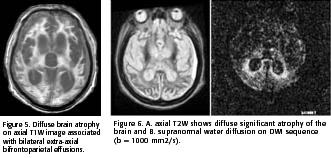

In January of 2003, a year and ten months after the onset of symptoms, the patient was kept under intensive care and underwent a second MRI. The T1W images demonstrated diffuse marked brain atrophy associated with frontoparietal subdural effusions (figure 5). The signal abnormalities in the basal ganglia were no longer apparent on T2W or DWI images (Figure 6).

Murata et al. (2002) discussed in their study the persistence of striatal and cortical hyperintensities on FLAIR and DWI images in the early and late stage of sCJD (2). In their study, the authors define the late stage of sCJD as more than 4 months after the onset of symptoms. Since the patient studied in our paper has such a long disease evolution and such profound brain damage, this might explain the disappearance of the striatal hyperintensities on T2W and DWI images. These suggest that the changes in the late stage of sCJD are unspecific and compatible with any encephalopathic process (8).

In conclusion, further studies are necessary to understand the pathophysiological mechanisms involved in the basal ganglia diffusion restriction in patients with sCJD. The role of MRI, mainly the T2W and DWI sequences is well established in the earlier stages of the disease process. In more advanced phases of the disease, when severe brain atrophy is often observed, the DWI sequence fails to demonstrate a specific pattern.